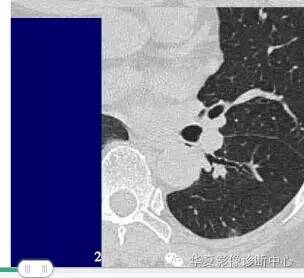

大家仔细看看这个中央不强化的腔内壁

你会发现内壁强化明显,边界清楚

一般这是炎性的脓腔,内层是肉芽肿,明显强化,分界清楚

癌肿的坏死一般是缺血性的,是肿瘤生长速度过快,中央带的血管受挤压,中央供血不足坏死的,一般边界模糊

内有内层强化,不会这么清楚

这是两者坏死的差异

内带强化带,边界清楚

但是这个其实整体看起来不是分叶征

只是一个一个的凸起